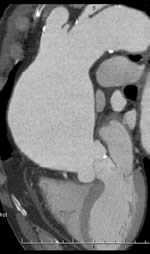

Image Diagnosis: Thoracic Aortic Dissection And Thoracic ...

And Thoracic Aortic Aneurysm Sundeep R Bhat, MD Gus M Garmel, MD of Surgery (Emergency Medicine) at Stanford University School of Medicine in CA. He is also a Senior Editor for The Permanente Journal. E Thoracic Aortic Dissection and Thoracic Aortic Aneurysm Figure 2. Thoracic Aortic ... Read Document